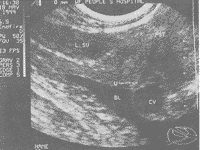

中国超声医学杂志000127 患者男,47岁,因尿频,尿急,会阴部不适半年余就诊。膀胱充盈后,经腹壁扫查,未见明显异常。后用经直肠超声扫查,(探头频率6.5MHz),于膀胱颈口探及8.6mm×8.7mm无回声,凸入膀胱,边清,形态规则,包膜完整,内透声好(图1)。排尿后无回声区无明显变化,膀胱内残余尿量约10ml。B超诊断:膀胱颈口囊肿。后经膀胱镜检查证实并行电切术。

CY:囊肿,BL:膀胱,U:尿道,PST:前列腺,L.SV:左侧精囊

图1 膀胱颈口囊肿